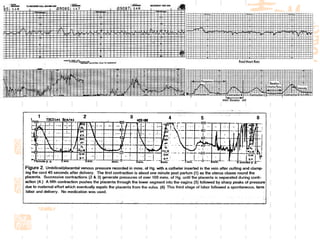

Characteristics of the   power Intensity is greater in the fundus Average 24mmHg Well synchronized  Frequency  Duration 60s regular Rhythm and force Basal resting pressure   12-15mmHg

Fetal monitoring

External and internal monitor